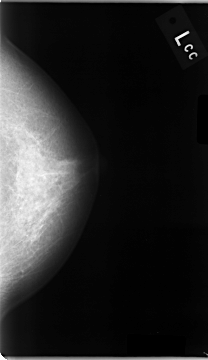

C_0005_1.LEFT_CC

LEFT_CC LINES 4680 PIXELS_PER_LINE 2696 BITS_PER_PIXEL 12 RESOLUTION 50 NON_OVERLAY